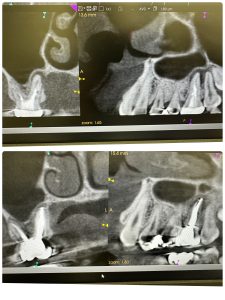

パラタルプレートの再生、ヤグレーザー併用の根管治療のみ

経過みないとね、自然治癒力は素晴らしい!

外科処置の勇み足にならない為の良い症例

最小侵襲で治癒導くが重要

CT撮影は、算定要件満たしてない為に無料😭

咀嚼に耐え得る歯は保存!